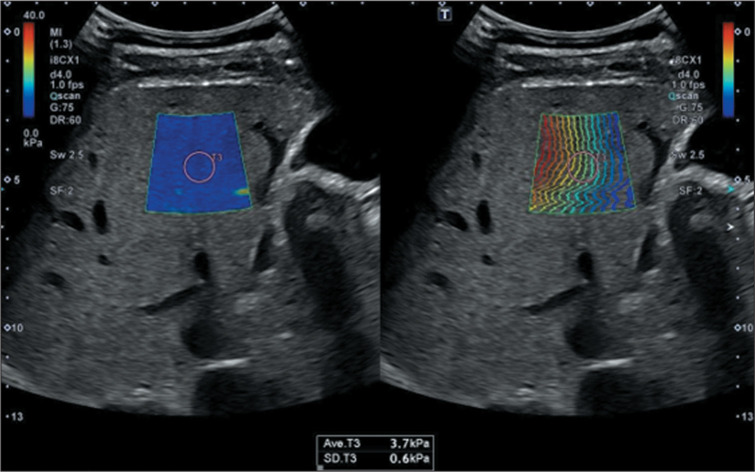

This study aimed to systematically review the highest-quality evidence regarding the cutoff value in kPa for the diagnostic accuracy of ultrasound-based liver elastography in comparison with reference standards, including magnetic resonance imaging (MRI), computed tomography, and liver biopsy. In addition, we assessed the presence of hepatocellular carcinoma (HCC) and its associated implications in clinical and diagnostic contexts. We conducted a search using Medical Subject Headings across PubMed, Embase, Cochrane Library, Web of Science, Scopus, and Lilacs for articles published up to June 6, 2024. Of 1,131 studies identified, 33 were eligible and 8 met the quality criteria, as evaluated with the "RTI Item Bank" and "QUADAS-2" tools, following the PICO strategy. The mean elasticity of the liver parenchyma among patients with confirmed HCC was 18.77 kPa (95% CI: 16.28-21.27), making ultrasound liver elastography useful as a predictor of the diagnosis by gold-standard methods such as MRI. Ultrasound elastography is a low-cost, accessible, and noninvasive diagnostic tool capable of estimating liver elasticity in patients with HCC. However, due to the heterogeneity of the articles included in this review, further prospective studies are needed in order to confirm and standardize a cutoff stiffness value for early HCC screening, which could improve patient outcomes, particularly in resource-limited settings.

Abstract Image